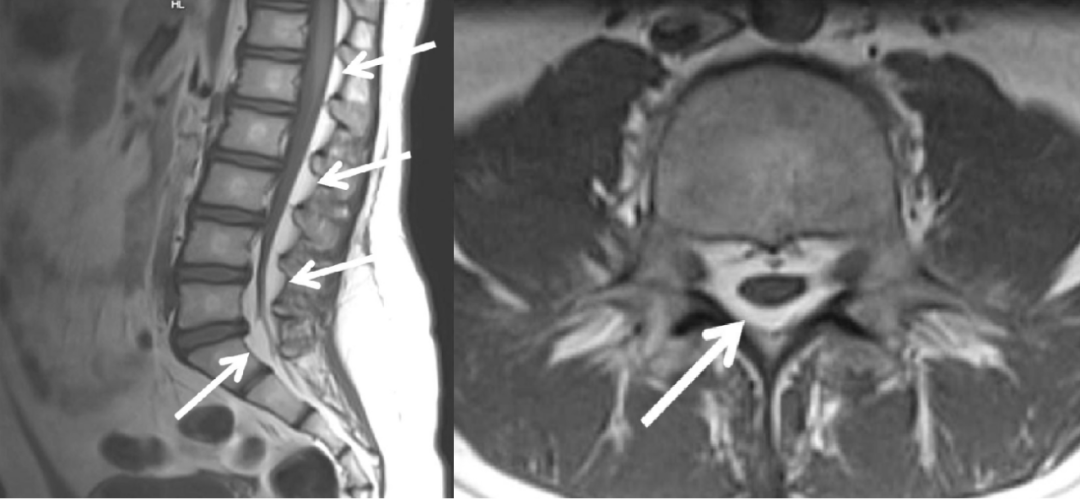

病例一

男,45 岁,1 年前出现慢性腰痛、双侧大腿麻木和无力感。临床查体无神经功能缺损。

本次腰椎 MR 检查:你发现了什么?

4.5 年前和现在的腰椎 MR T2WI 轴位对比:L4-L5 水平,现在的 MR 发现马尾神经位置前移,更加聚拢;而 4.5 年前的 MR 发现马尾神经位置靠后,分散。

回过头再看第一个病例,发现椎管内硬膜外脂肪增多,向前推挤马尾神经,使其相对聚拢

同样的,回头看第一个病例也会发现硬脊膜椎韧带,是由于硬膜外脂肪增多而把他显示出来